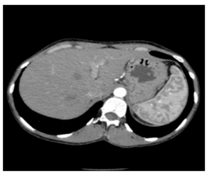

In this section, we present and analyze the results obtained with the proposed method, and compare it to methods proposed in similar works. The proposed watermarking system is implemented using MATLAB and executed on a Windows machine with the following characteristics: Intel R Core i5 processor, 4 GHz, 4 GB RAM, and Microsoft Windows 8 Professional operating system platform. In our experiments, we have used DICOM images of size 512 × 512 pixels as shown in Table 1.

Table 1.

Original images.